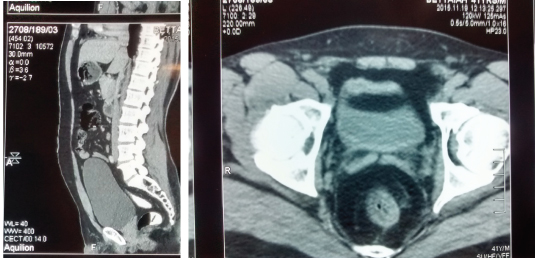

Colonoscopy was done which showed lesion in the posterior and lateral wall measuring about 4cm and 2cm from anal verge. Rest of the colon appeared normal. CECT abdomen showed circumferential irregular wall thickening about 4cm proximal to anal verge with enlarged left inguinal, mesorectal and left internal iliac lymph node enlargement without perianal fat stranding [Table/Fig-6a,b]. Chest X Ray showed no evidence pulmonary carcinoma. Bone scan was normal and tumour marker i.e., Carcinoembryonic antigen was not elevated. The patient was negative for HIV, HbsAg and HCV.

CECT showing circumferential irregular wall thickening about 4 cm proximal to anal verge with enlarged left inguinal, mesorectal and left internal iliac lymph node enlargement without perianal fat stranding (a = Coronoal section; b= Axial section).